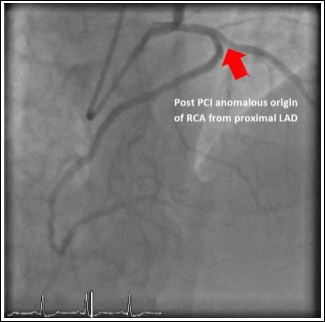

The third case was a 51-year-old male with no prior history of ischaemic heart disease presenting with unstable angina. His admission ECGs was unremarkable. Diagnostic coronary angiogram was done and it showed a right coronary artery arising from the proximal LAD. Mid LAD had severe diffuse stenosis distal to the origin of RCA. There was a 70% stenosis in the proximal RCA and a further 80% stenosis in the distal RCA (Figure 5). PCI to mid LAD and proximal RCA was done (Figure 6). It was an uncomplicated procedure and patient was discharged after 4 days of hospital stay. The echocardiography did not reveal any associated structural heart disease.

Figure 5: Anomalous origin of right coronary artery from the proximal left anterior descending artery and diffused lesion of the distal right coronary artery.

Figure 6: Anomalous origin of right coronary artery from the proximal left anterior descending artery (post PCI).